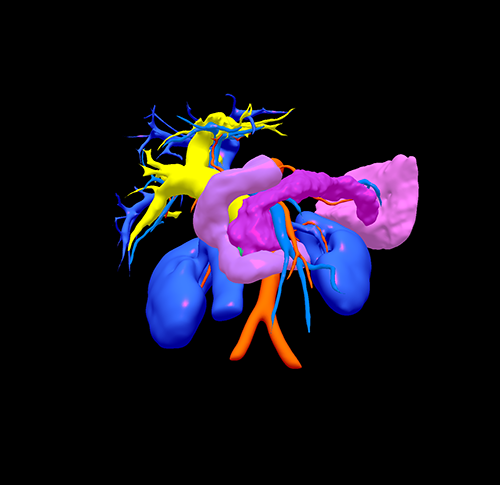

胰头癌-胰十二指肠切除